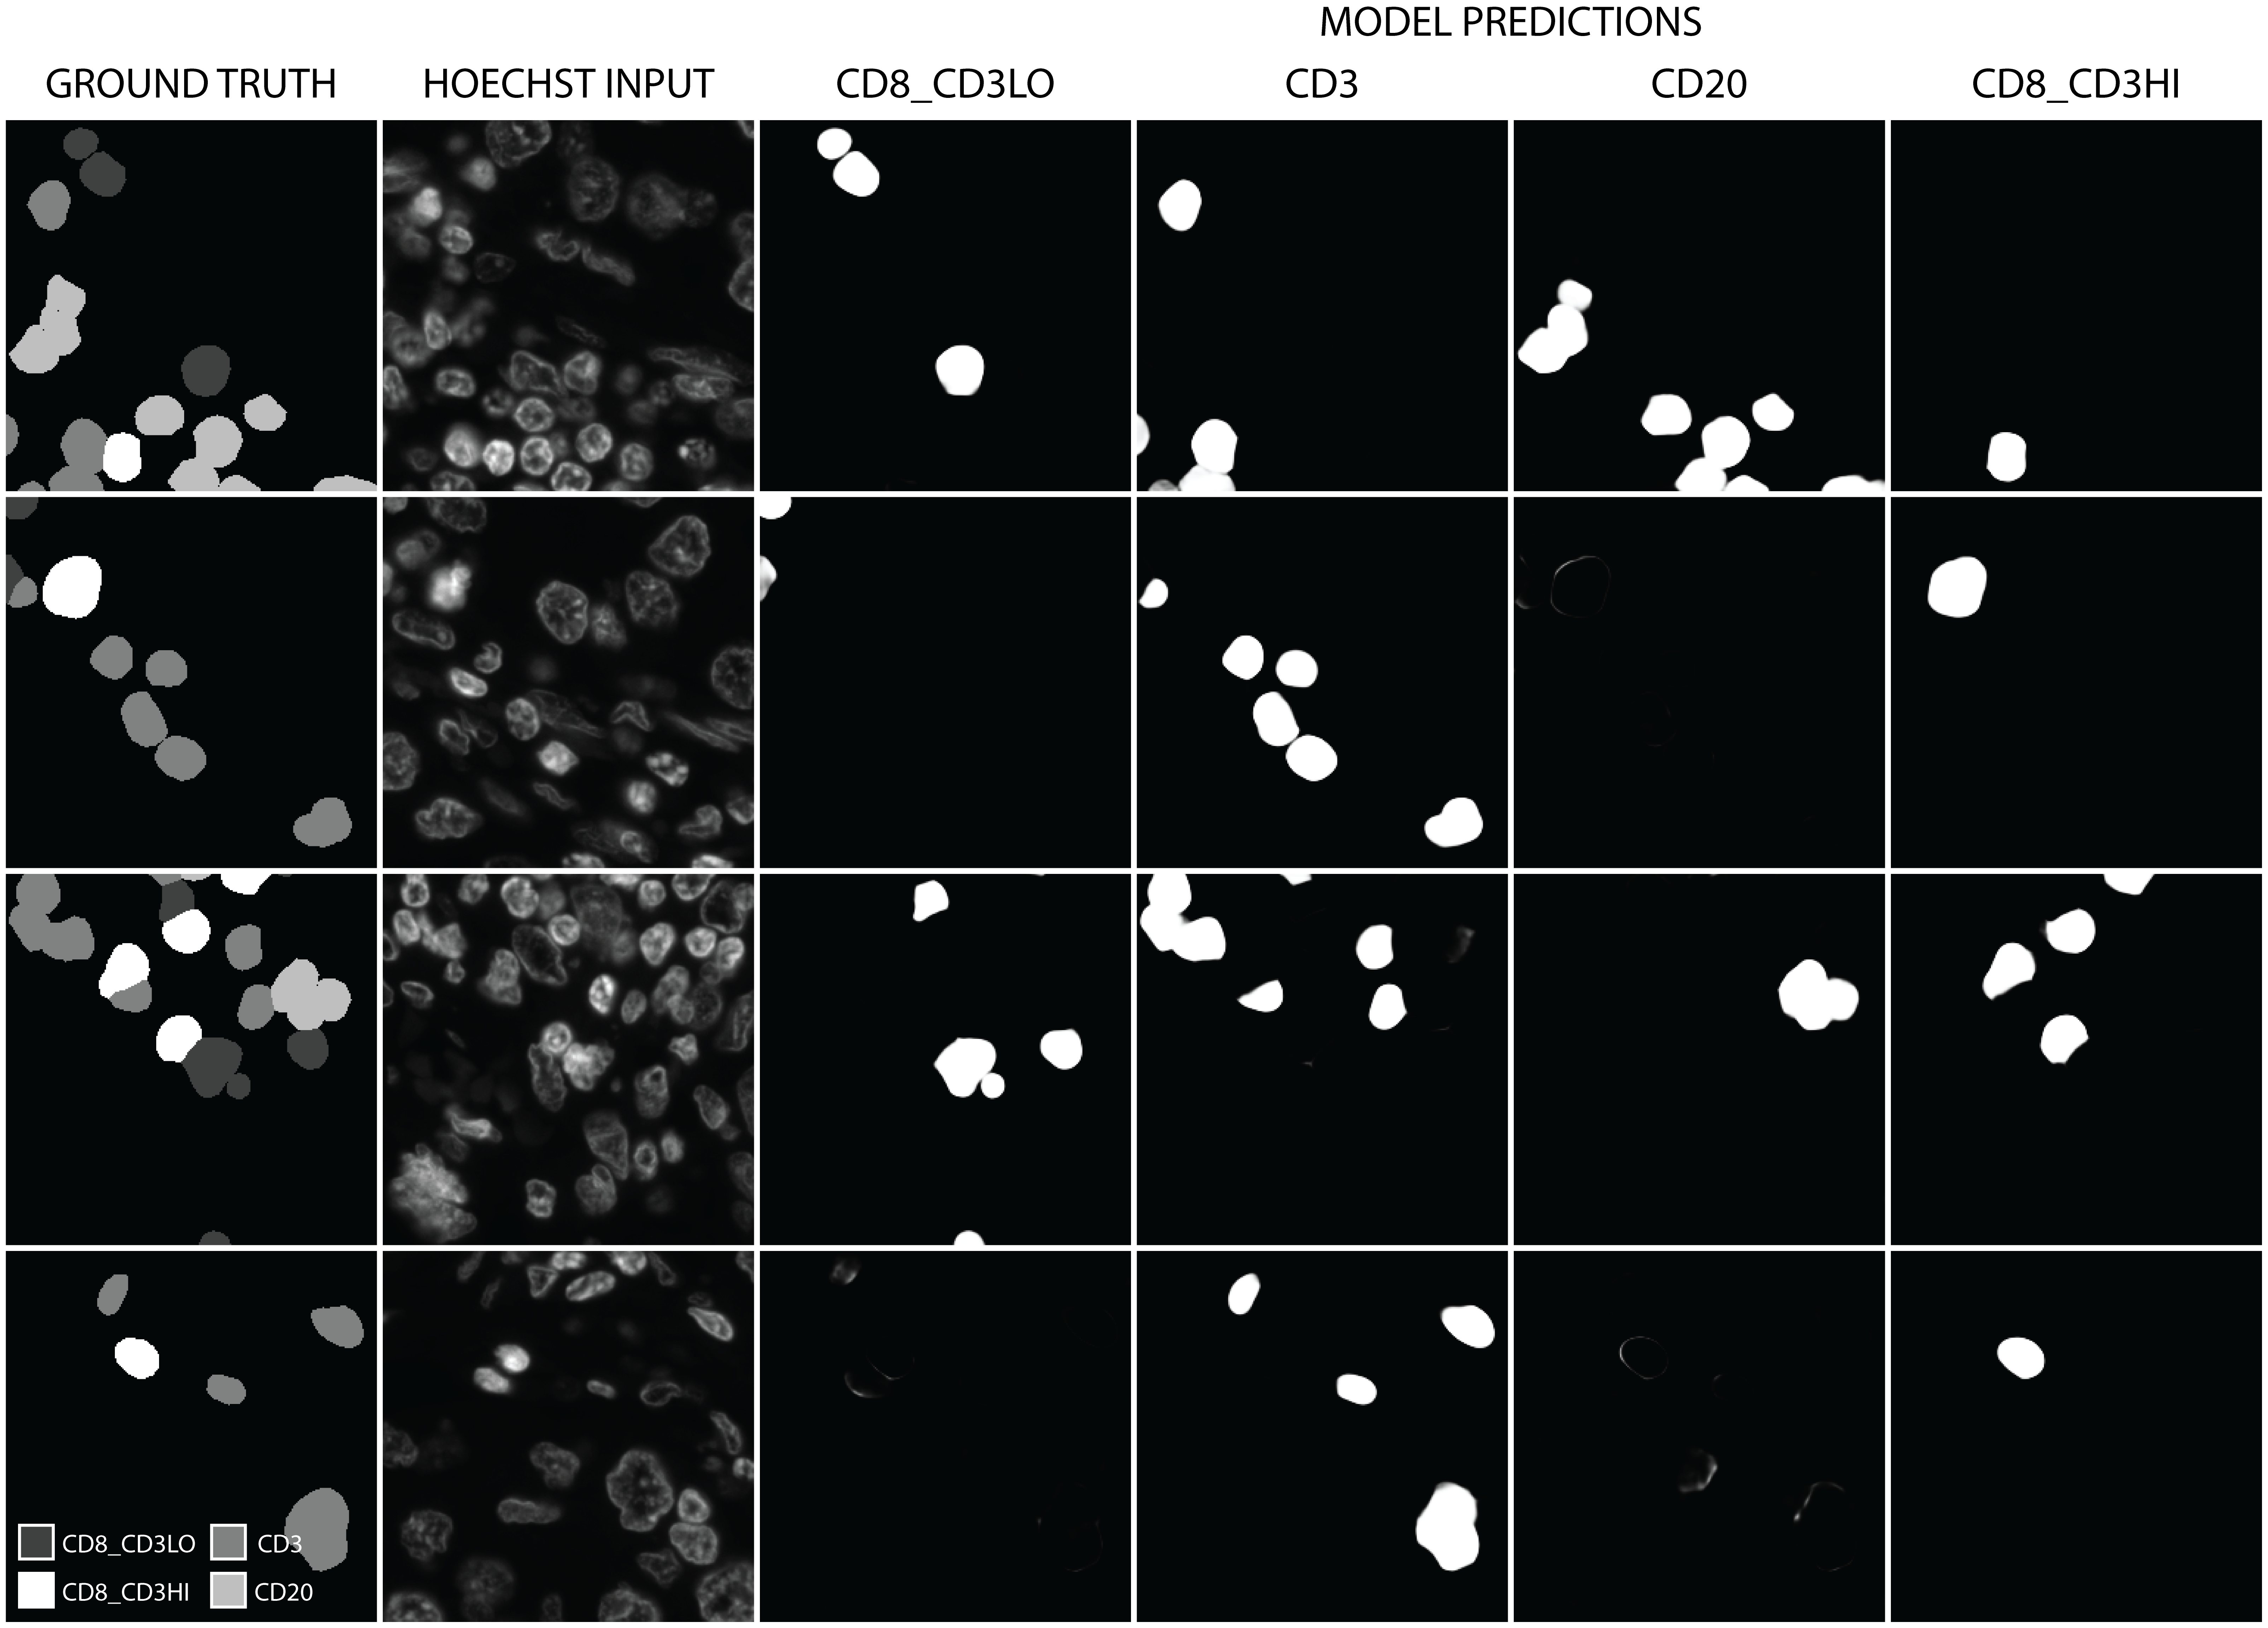

Table 2 shows the performance of our model according to these metrics. We achieve over 90% precision, recall and F1 score across all classes on the test set, showing excellent generalisation ability to unseen data with only a small decrease in performance compared to the training set. CD8_CD3HI expressing cells were the most difficult to classify, likely due to their lower representation across the training set. As expected, we see a small increase in performance across these metrics when evaluating the cell centroid classifications only, because in this case imperfect segmentation of regions at the edges of cells is disregarded. Figure 2 shows four random sample pairs from the test set, along with the model output predictions for each class – as we can see here, the segmentation is reliably good.